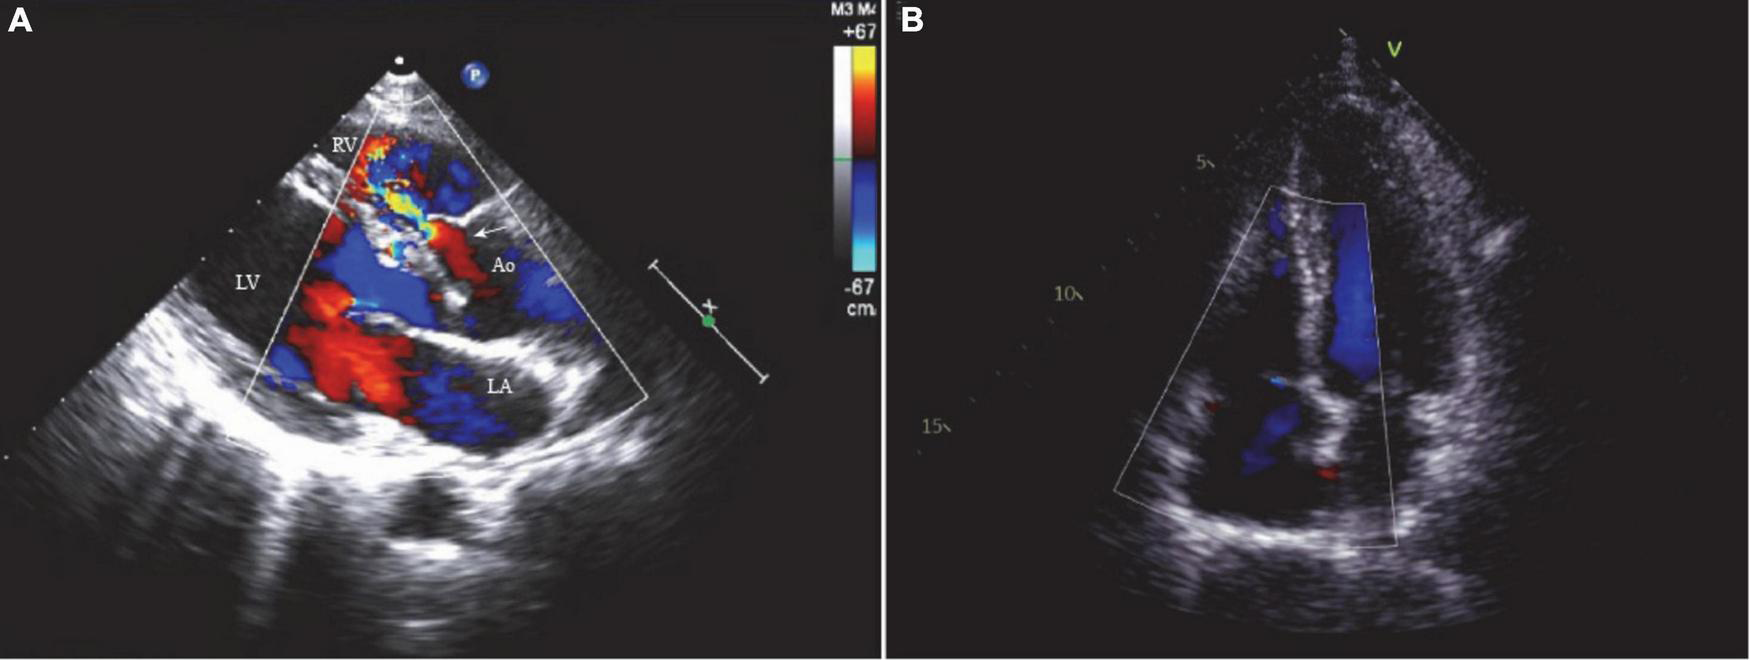

A 48-year-old female visited our clinic with complaints of dyspnea for 4 months. On arrival, her vital signs were stable, including a body temperature of 36.1°C, a heart rate of 96 beats/min, a respiratory rate of 20 breaths/min, and a blood pressure of 121/67 mmHg. Jugular vein distension or limb edema was absent. A continuous third-degree heart murmur was noted over the left sternal border. She was diagnosed with SVA at the age of 15. However, she was asymptomatic until 6 years ago, when she experienced occasional shortness of breath and fatigue. Surgery was recommended, but she accepted medical therapy for fear of cardiac surgery. Four months prior to her presentation, her symptoms were exacerbated, and she developed dyspnea. Transthoracic echocardiography (TTE) showed a 10.6 mm × 9.6 mm dilated SVA with a ruptured right coronary sinus into the right ventricular outflow tract (RVOT) (Figure 1A). The diameter of the aortocardial shunt was approximately 5.0 mm, and turbulent blood flow was observed from the aorta to the RVOT with a peak flow velocity of 4.9 m/s and a pressure gradient of 96 mmHg. The aortic regurgitation was traced, but the aortic valve anatomy and function were normal. The atria and ventricles remained normal in size. The ejection fraction of the left ventricle was 64%. No defects involving the atrial septum or the ventricular septum, endocarditis, or severe valvular regurgitation were noted on TTE. However, transesophageal echocardiography (TEE) revealed a small infundibular VSD with no other congenital pathology.

(A) The two-dimensional echocardiogram showed a 10.6 mm × 9.6 mm ruptured sinus of Valsalva aneurysm (right coronary sinus) and a 5.0 mm aortocardiac shunt (white arrow). (B) No residual shunt or valve regurgitation noted on the postoperative echocardiogram. LA, left atrium; LV, left ventricle; RV, right ventricle; Ao, aorta.